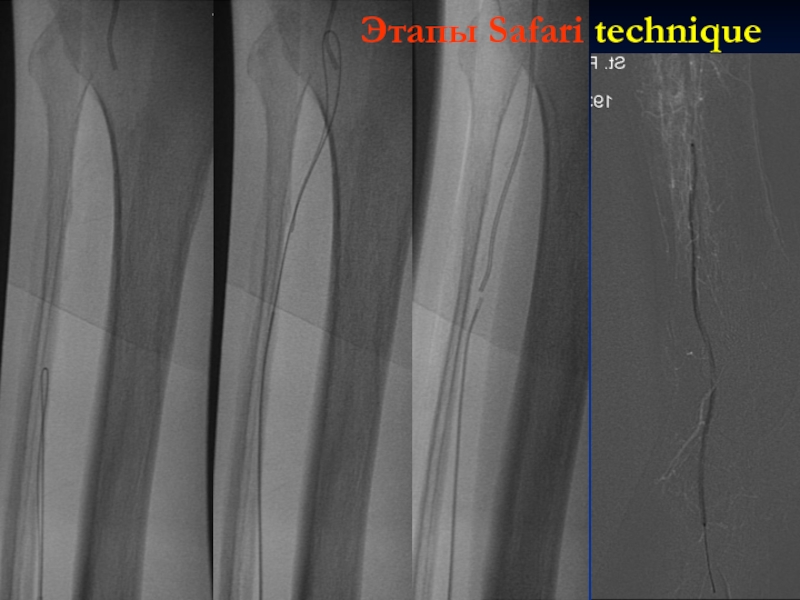

Слайд 24Этапы Safari technique

Этапы Safari technique